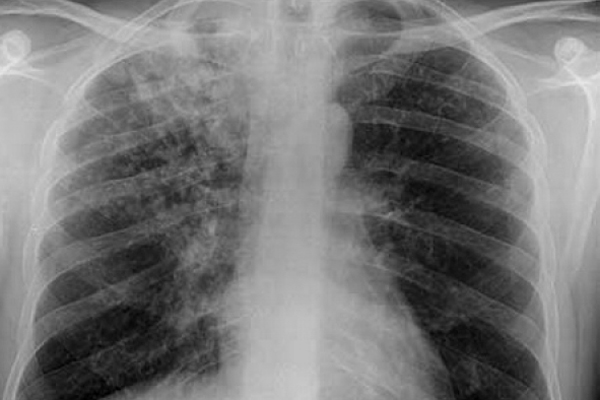

Republica Moldova va obține în următorii doi ani 15,8 milioane de euro din partea Fondului Global de Combatere SIDA, Tuberculozei și Malariei. Pentru controlul HIV/SIDA este prevăzută suma de 7,1 milioane de euro, iar pentru controlul tuberculozei – 8,7 milioane de euro, transmite IPN.

Potrivit unui comunicat de presă al Ministerului Sănătății, Muncii și Protecției Sociale, vor fi finanțate activitățile incluse în programele naționale de profilaxie și control al tuberculozei și infecției HIV pentru anii 2016-2020.

Republica Moldova a depus aplicațiile pentru continuarea granturilor Fondului Global destinate prevenirii și controlului TB și HIV/SIDA la începutul anului 2017. Începând cu anul 2003, Fondul Global a acordat Republicii Moldova investiții în valoare de aproximativ 115 milioane de dolari pentru susținerea programelor naționale de prevenire și control al tuberculozei și HIV/SIDA.